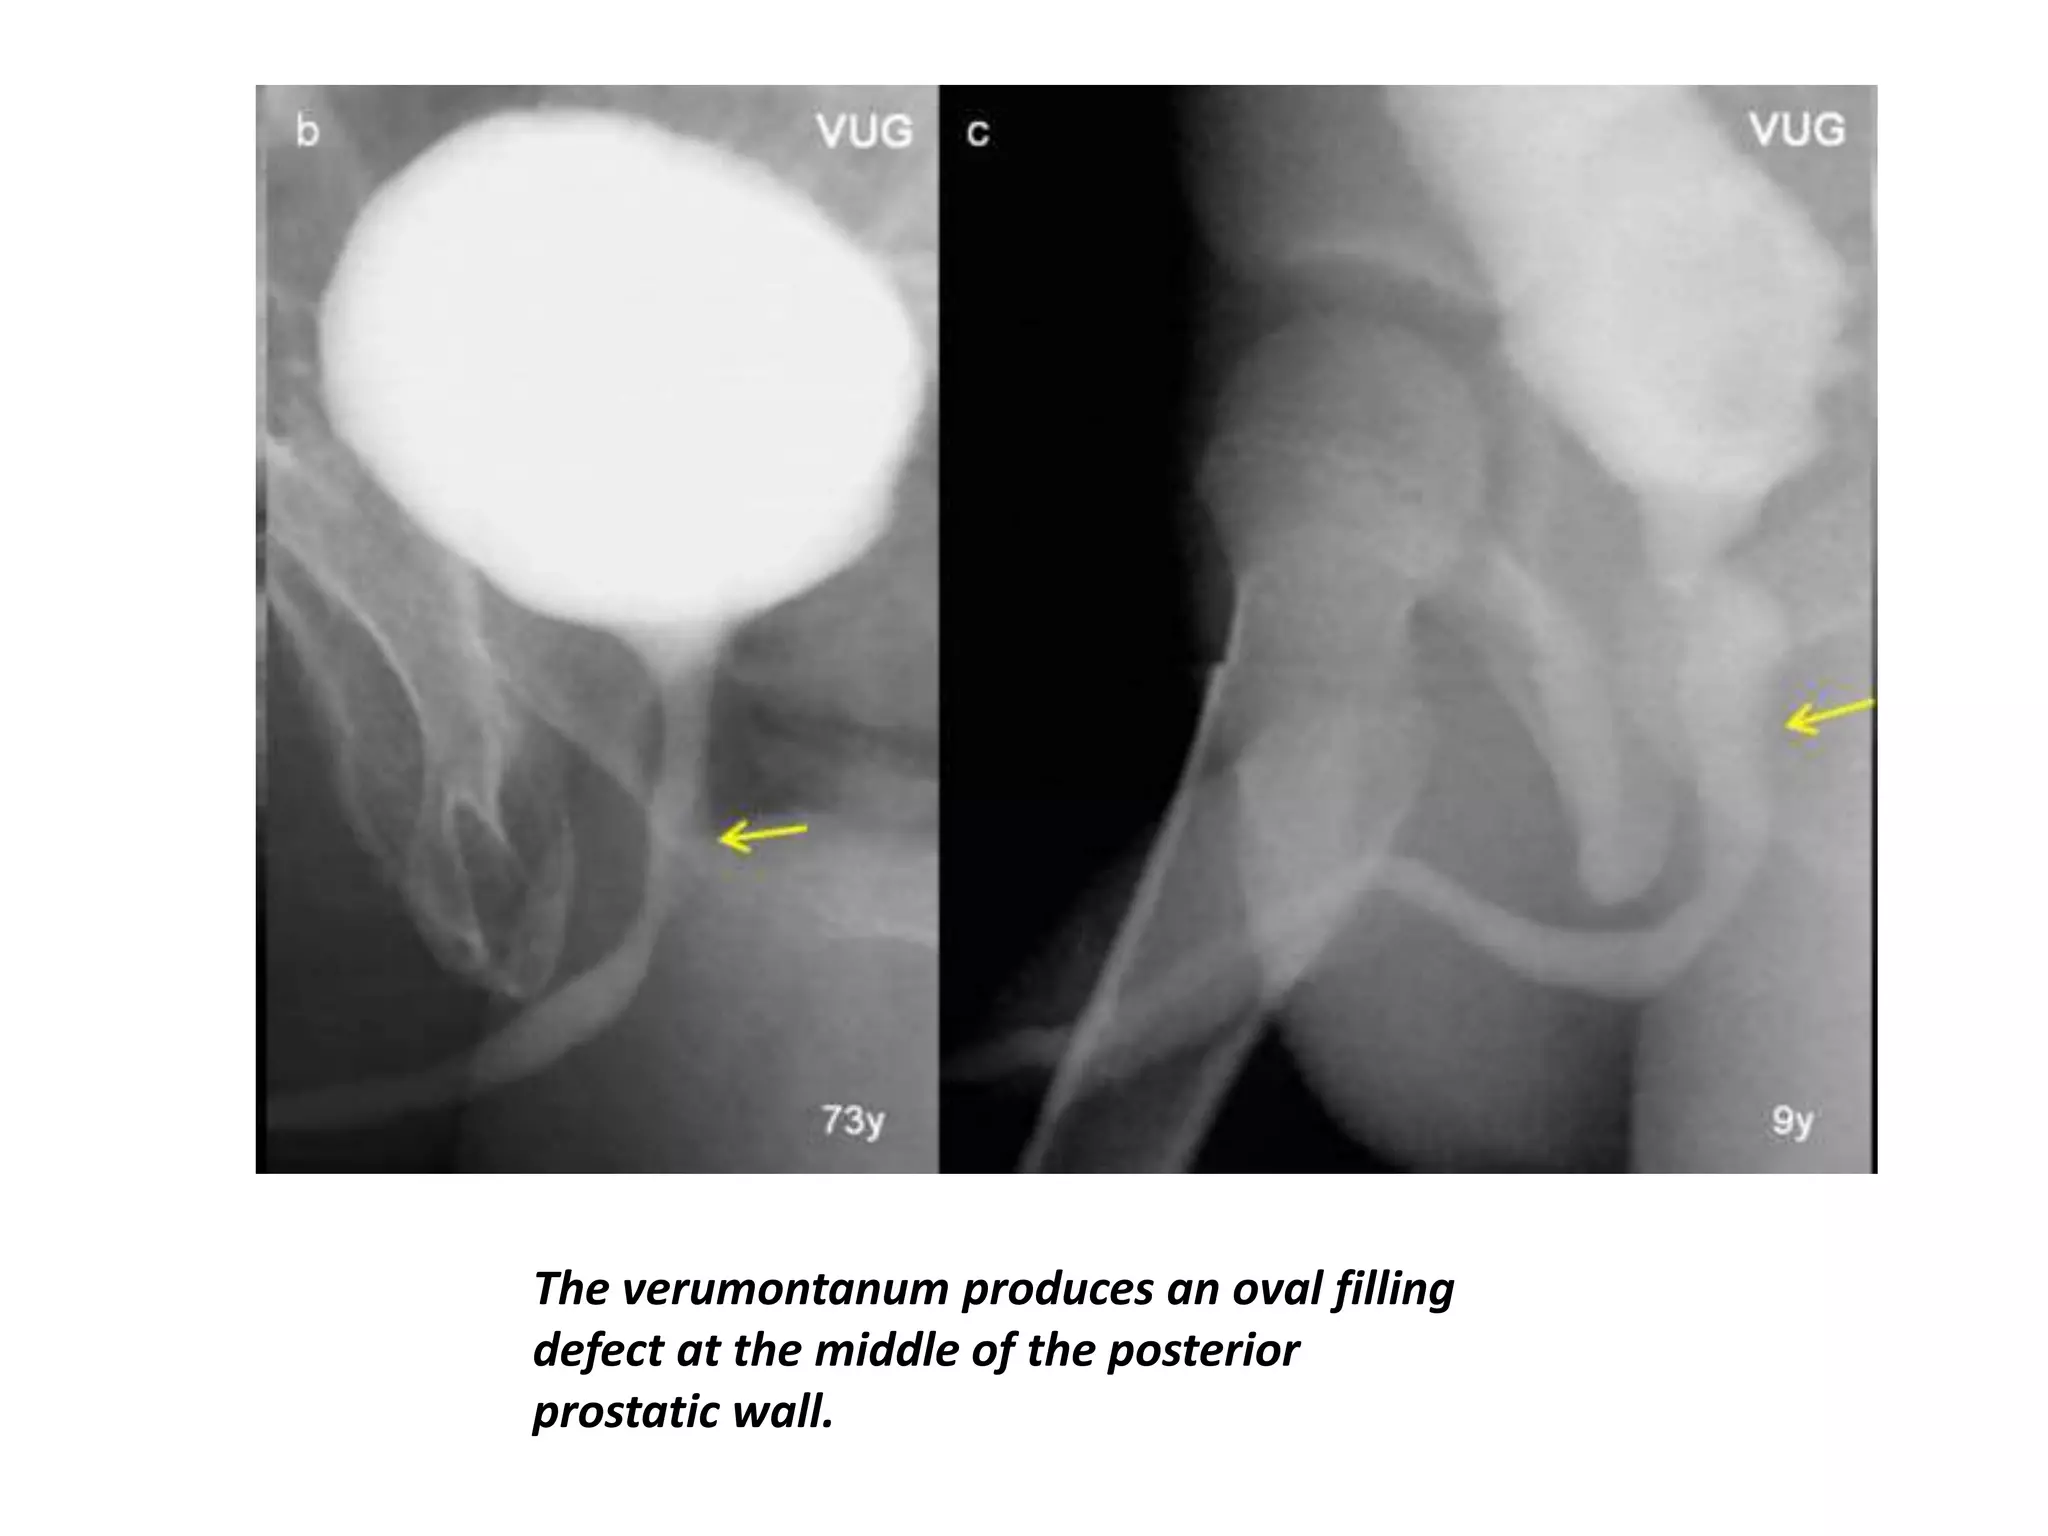

• Verumontanum is a

1-cm-long ovoid

mound that lies in

the posterior wall

of the prostatic

urethra.

The verumontanum produces an oval filling

defect at the middle of the posterior

prostatic wall.